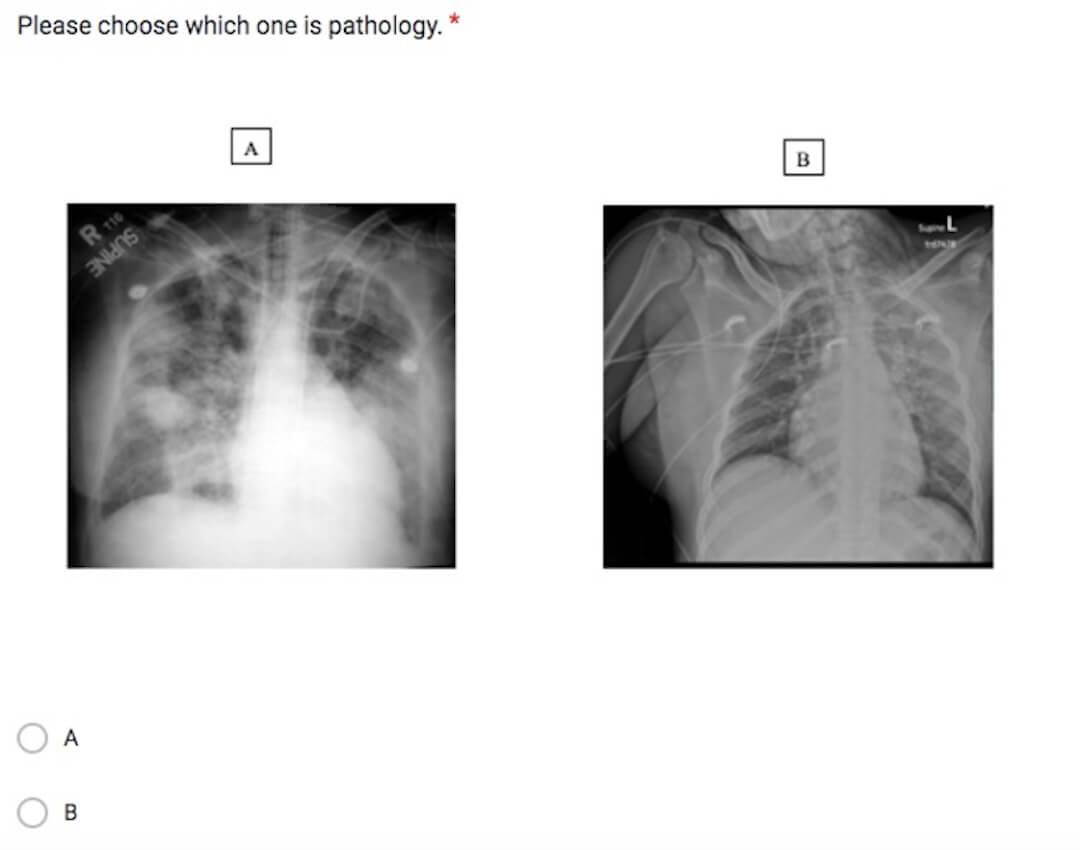

“Coming previously from Toronto, where the demographic was mostly Caucasian, Dr. Maresky had been collecting these images since he started at Temple in North Philadelphia, which is predominantly an African-American community,” says Udongwo. Hair artifacts (unwanted distortions in X-ray images caused by hair) not only make it difficult to identify what's being examined, which can lead to misdiagnoses, but they also show examples of Black hairstyles not properly represented in the medical education and research communities.

To bridge this gap, Dr. Maresky and Udongwo dived right into their research, examining hairstyles in chest X-ray (CXR) and MRI images. They started by identifying the five most-popular Black hairstyles (small braids, large braids, small twists, large twists, and locs) and created a slideshow with examples of how each hairstyle looks on a radiograph, CT slice, and/or chest X-ray. Udongwo then created a survey to see how well physicians could differentiate these hairstyles from pathology, like pneumonia, tuberculosis, or pneumothorax.